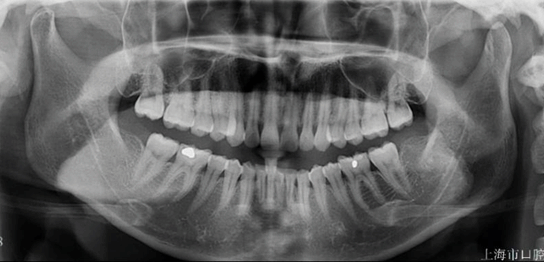

图1.正畸生物力学机制及其临床应用

本项目借助 Unity 3D、Studio Max 等工具构建虚拟患者及其牙移动过程,基于复旦大学口腔医学院正畸教研室的临床真实病例,高度模拟还原牙、牙根及牙槽骨等生物学结构。学生进行矫治力支点、方向的设计和制定,形成特定的正畸矫治力系统。通过虚拟动画展示在该系统下的牙移动方式,可视化展示作用力线与牙齿的旋转中心、阻抗中心之间的相互关系对牙齿移动类型的影响,有助于学生理解生物力学相关基本概念及其在临床实践中的应用。

步骤5在种植钉制备操作界面,完成种植钉的植入,过程中需关注虚拟患者是否存在酸痛不适,并学会根据患者体征及影像资料实时调整种植钉植入方向